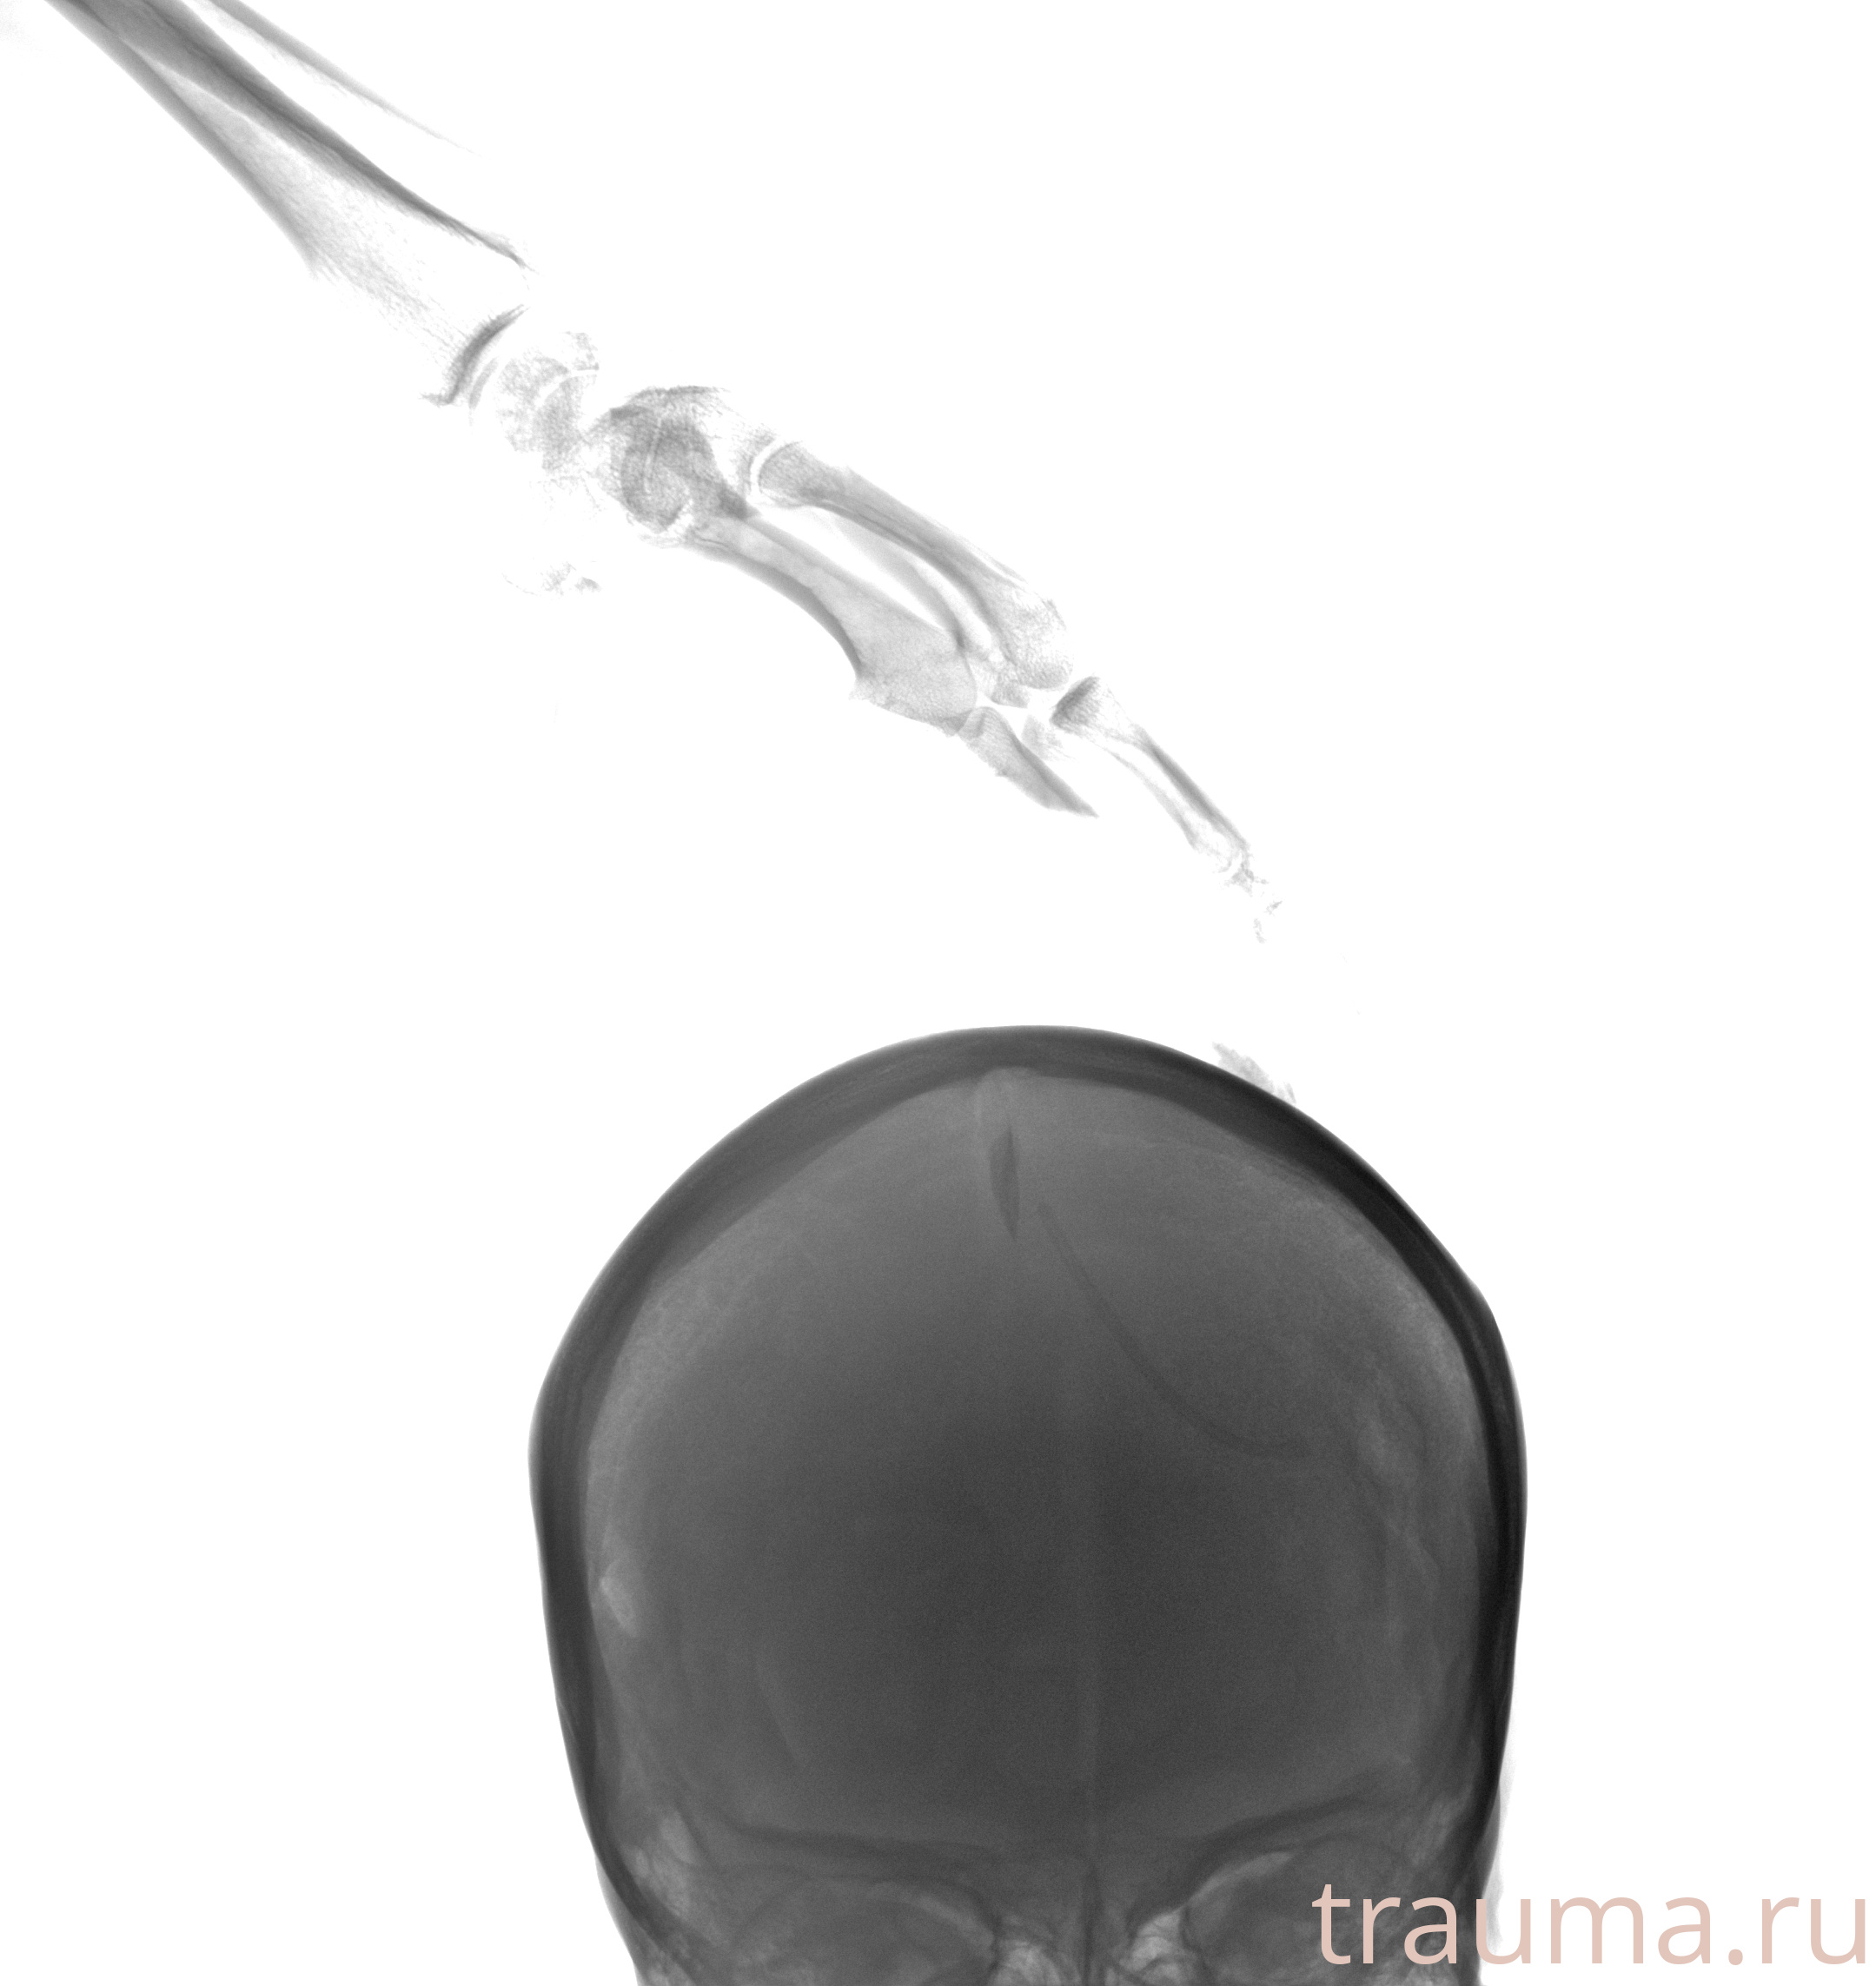

Рентгенограммы

Рентген на дому: по вашему адресу приезжает врач-рентгенолог, травматолог-ортопед с мобильным рентгеновским аппаратом, проводит диагностику травмы или заболевания, делает необходимые рентгенограммы, дает рекомендации по дальнейшему лечению. Получить качественные снимки в домашних условиях возможно благодаря уникальной методике, разработанной МосРентген Центром для института  Склифосовского